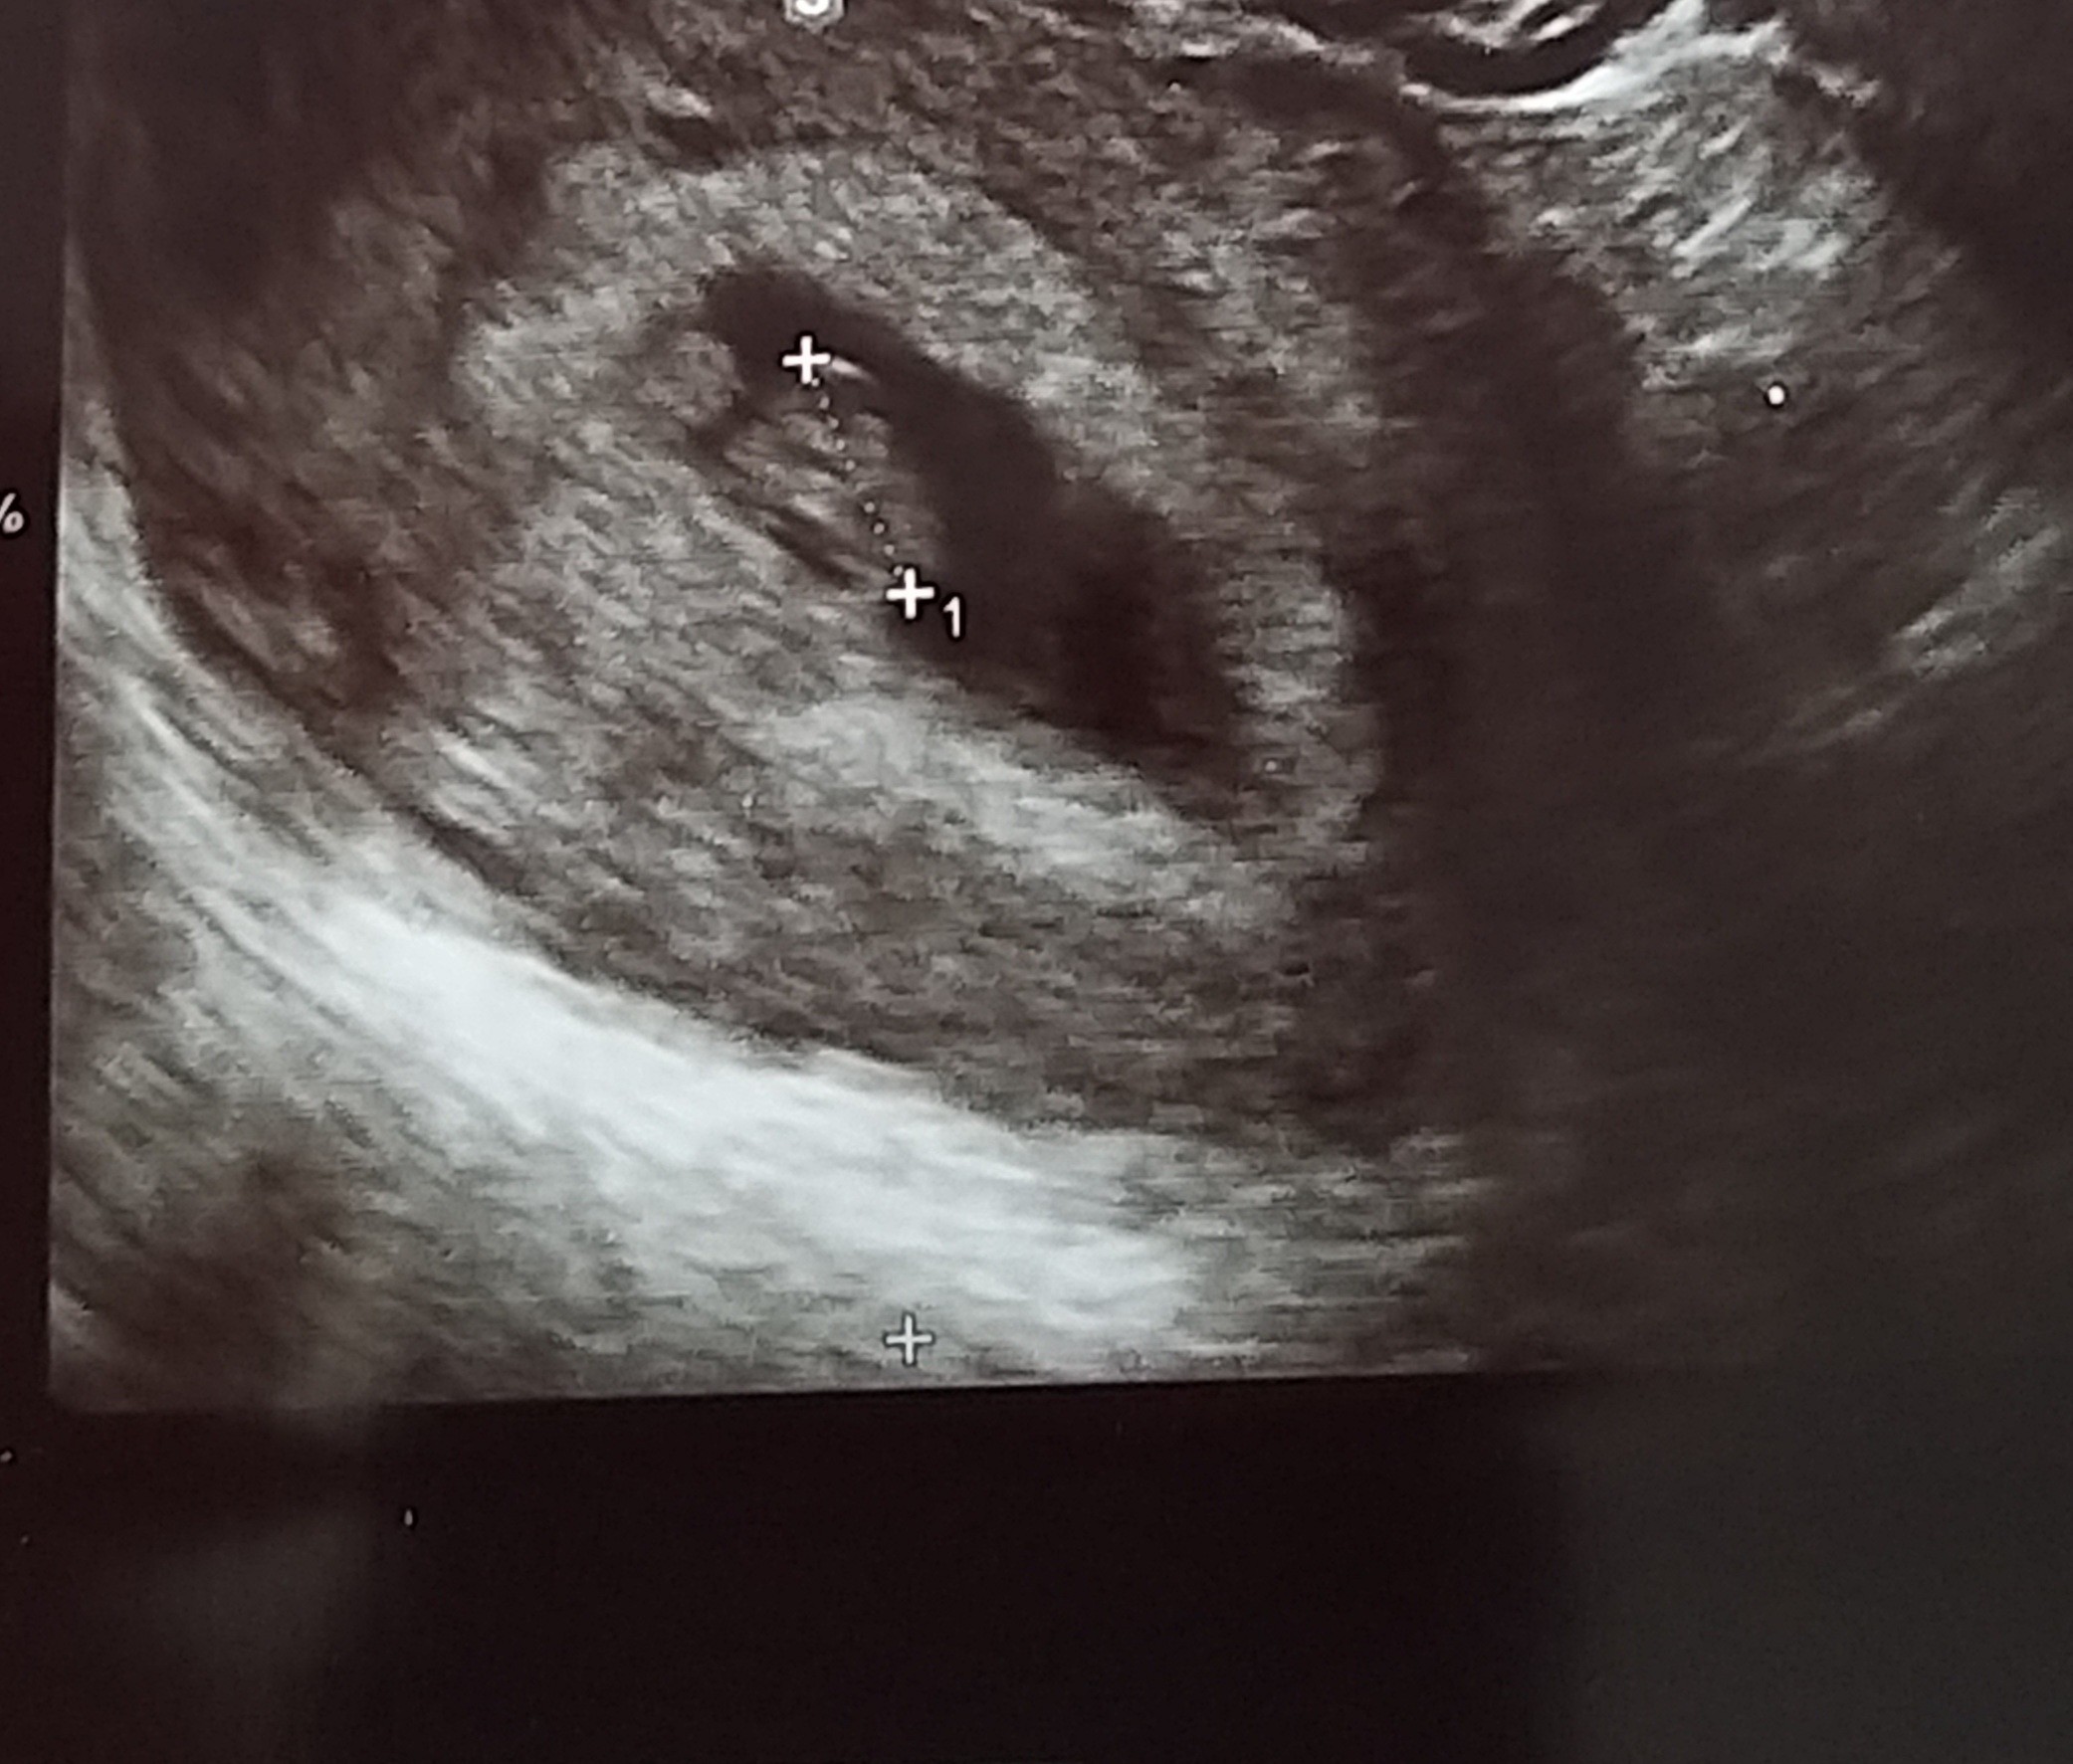

Moja fasolka ma już 1 cm :) dwa dni temu mieliśmy kolizję i chciałam upewnić się, że nic złego się nie wydarzyło od mojej ostatniej wizyty.

Załączniki

• 20210608_124646.jpg

20210608_124646.jpg

459,4 KB · Wyświetleń: 99